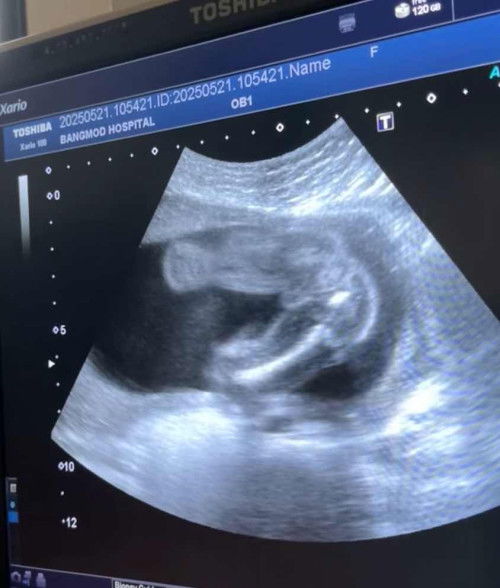

ทุกคนคิดว่าเจ้าจิ๋วจะเป็น ญ หรือ ช

ภาพซาวด์ตอน22วีค คือหมอบอกว่าน้องอาจจะเป็นเพศหญิงแต่พอให้คนอื่นดูหลายคนก็ว่าเหมือนของลูกชายตัวเองเลย ตอนนี้เลยเริ่มลังเลแล้วว่าเจ้าจิ๋วจะเป็นหญิงหรือชาย ช่วยดูหน่อยยย

หมอบอกว่าผู้ชาย จริงไหมค่าแม่ๆ #ทีมกันยา68❤️❤️

#แม่มือใหม่ #ขอบคณสำหรับคำตอบล่วงหน้านะคะ

สวัสดีค่ะแม่ๆ อยากรู้ว่าได้ผู้ชายหรือผู้หญิงแม่ๆช่วยดูหน่อย หมอบอกว่าผู้ชาย จริงไหมค่ะ❤️